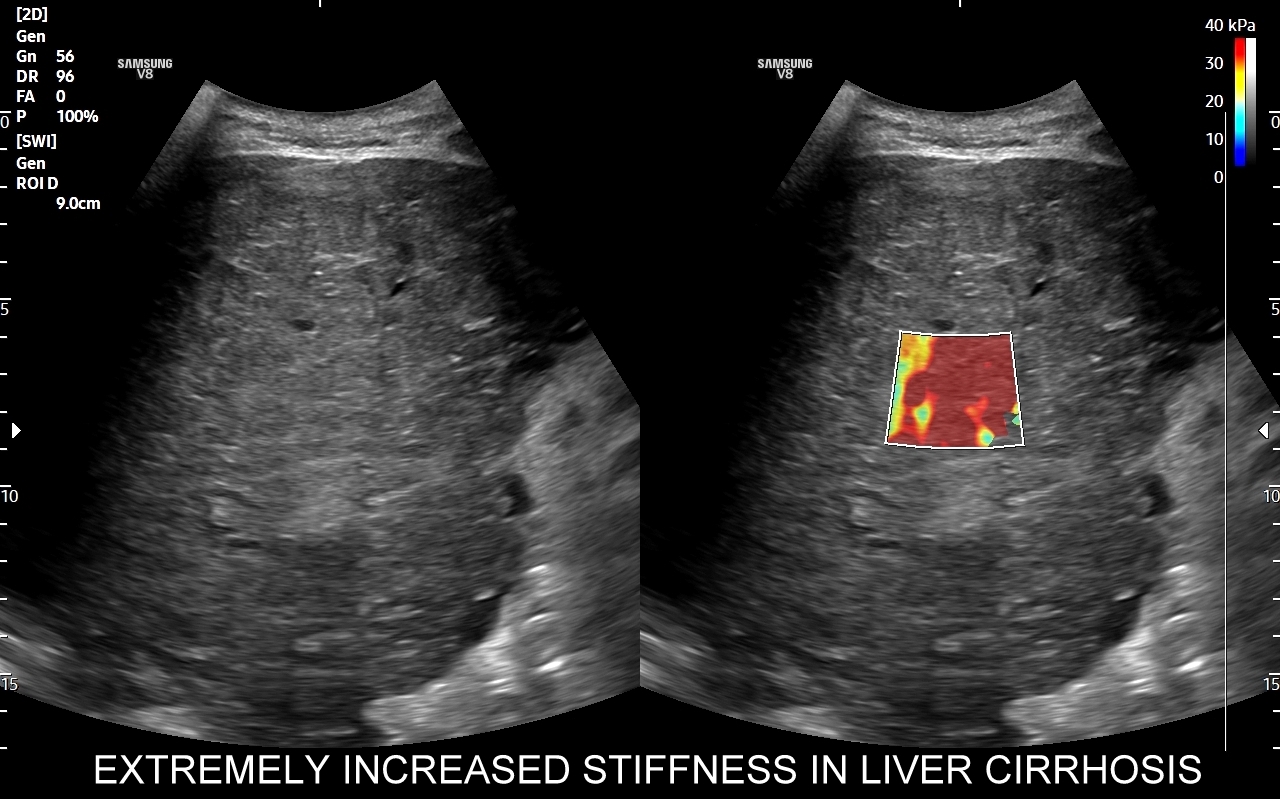

Elastografia jest metodą diagnostyczną oceniającą sztywność i spoistość tkanek. Istnieje kilka rodzajów technik elastograficznych. W przypadku badania miąższu wątroby wykorzystuje się technologię opartą o prędkość rozchodzenia się fali poprzecznej pod wpływem zastosowania impulsu mechanicznego. Otóż im tkanka jest sztywniejsza tym wyższa jest prędkość rozchodzenia się fali. Opisaną metodę określa się jako shear wave imaging (SWI).

Na przestrzeni czasu metoda SWI ulegała ewolucji. Jej starsza odmiana to tzw. Fibroscan, który jest badaniem „na ślepo”, gdyż nie umożliwia precyzyjnego wyboru miejsca oceny miąższu wątroby. Odmianą najnowszą i wysoce precyzyjną jest elastografia 2D-SWE (2D sheer wave elastography). W badaniu 2D-SWE możliwy jest wybór konkretnego miejsca pomiaru w obrębie wątroby; dodatkowo generowana jest mapa kodowaną kolorem odpowiadająca mnogim punktom pomiaru, które następnie w trakcie post-processingu można wybrać w celu uzyskania dokładnego i wiarygodnego wyniku.

W jakim celu wykonywana jest elastografia wątroby? Elastografia 2D-SWE precyzyjnie ocenia sztywność miąższu wątroby, która to wzrasta w procesie włóknienia na tle przewlekłych schorzeń narządu, np. zapaleń. Badanie pozwala w ten sposób ocenić stopień zaawansowania zwłóknienia lub marskości wątroby. Dokładność oszacowania zwłóknienia w elastografii 2D-swe jest na tyle precyzyjna, iż zastępuje ona w omawianym wskazaniu medycznym biopsję wątroby.